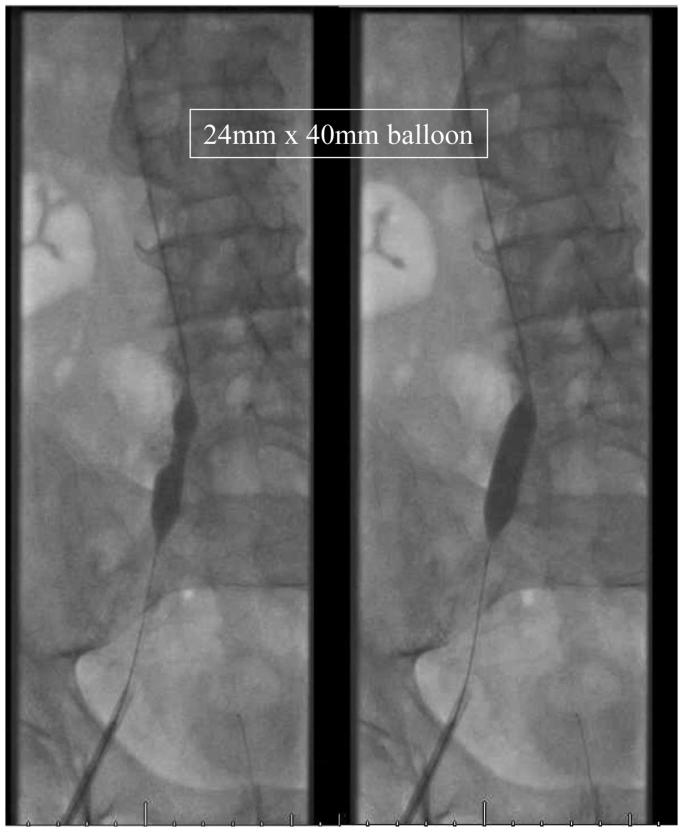

More than 10 million cases of venous thromboembolisms are reported on an annual basis and are major contributors to morbidity and mortality. Studies have found that ≤90% of pulmonary embolisms originate from the abdominal and lower extremity veins. The mainstay of venous thromboembolism treatment has been, and still continues to be, anticoagulation. However, for patients for whom anticoagulation is contraindicated or has failed, physicians have turned to surgical innovations such as inferior vena cava (IVC) filters to create partial interruption of the IVC. Before the invention of IVC filters, the Adams-DeWeese clip was developed to create caval interruption, which allowed for venous return while preventing pulmonary emboli from distal veins. We report a case of endovascular release of a long-term Adams-DeWeese clip, which had caused IVC occlusion and debilitating bilateral lower extremity swelling.

每年报告的静脉血栓栓塞病例超过1000万,是发病和死亡的主要原因。研究发现,≤90%的肺栓塞起源于腹部和下肢静脉。静脉血栓栓塞治疗的主要方法一直是且仍然是抗凝治疗。然而,对于抗凝治疗禁忌或失败的患者,医生已转向诸如下腔静脉(IVC)滤器等手术创新方法,以部分中断下腔静脉。在IVC滤器发明之前,Adams-DeWeese夹被开发用于造成腔静脉中断,在防止远端静脉肺栓塞的同时允许静脉回流。我们报告了一例长期植入的Adams-DeWeese夹血管内释放的病例,该夹子导致了下腔静脉阻塞和双侧下肢严重肿胀。